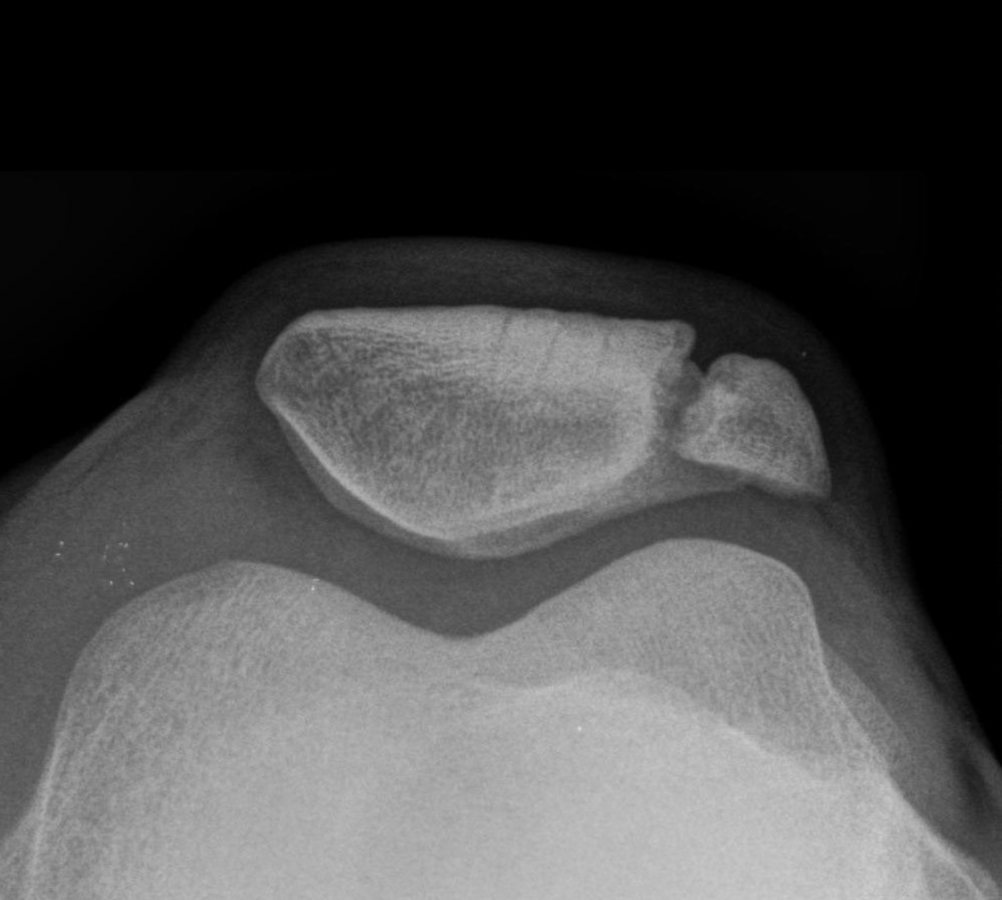

Eine Fraktur? Weit gefehlt. Bei einer Patella bipartita verschmelzen die Ossifikationskerne nicht. Eine Fraktur? Weit gefehlt. Bei einer Patella bipartita verschmelzen die Ossifikationskerne nicht. © wikimedia/Hellerhoff